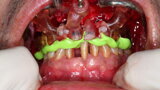

Compromised maxillary dentition treated with Straumann Pro Arch and a digital workflow